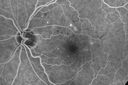

70 year old man with diabetes. OCT scan showed edema vision is 20/25 and the patient is not bothered. The edema did not progress